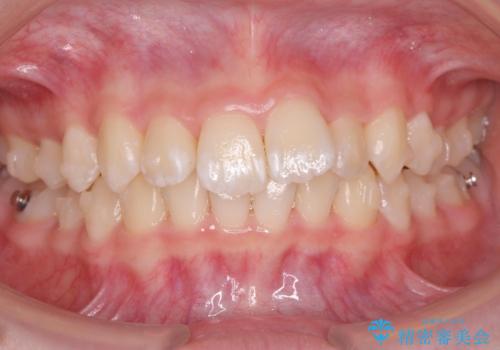

子供の出っ歯 生え代わりと成長期を利用して非抜歯で矯正

- 出っ歯を主訴に来院。

生え代わりを待ってから矯正を始めました。

特に右側のかみ合わせがずれていたため、上の奥歯を後ろに下げています。

下顎も前方に成長し、前歯のかみ合わせも同時に深かったのを浅くすることができました。

矯正は成人でも可能ですが、成人矯正よりも、有利なことがたくさんあります。

10代で矯正を行うと歯の動きも動きやすく、骨の付いてくる度合いもとてもよく、歯肉退縮など副作用が少ないのでお勧めです。移動も早いため、矯正治療期間も短めです。